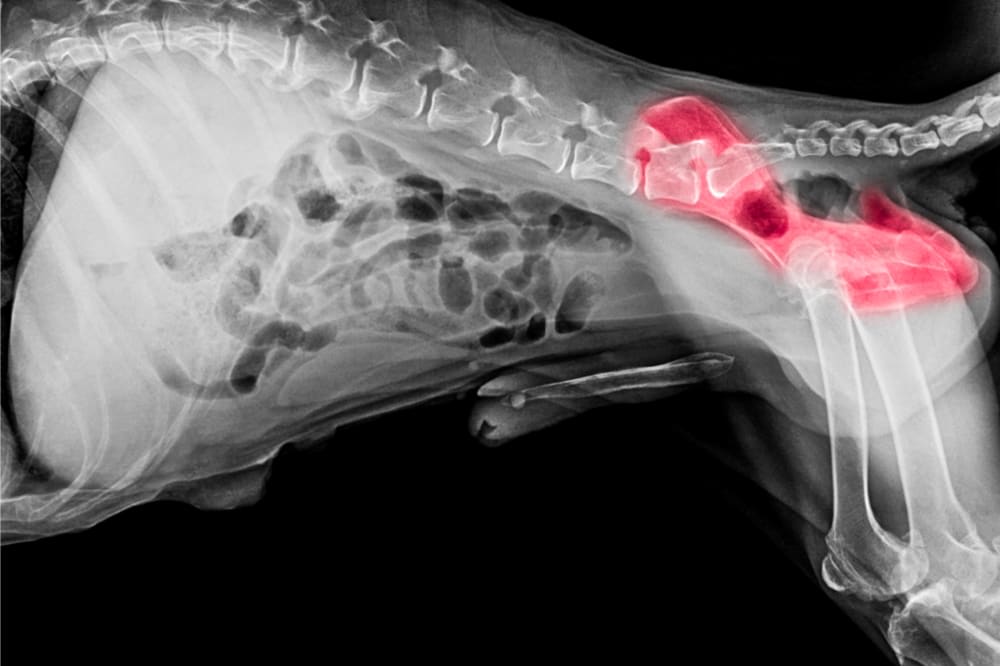

X-rays are one of the most useful and widely used tools in both human and veterinary medicine. X-rays allow veterinarians to see your pet's bones, tissues, and internal organs, allowing them to diagnose problems such as broken bones, bladder stones, swallowing foreign objects, and more.

X-ray images can help vets to spot some tumors, pregnancy, and enlarged organs which may lead to a diagnosis such as heart disease or cancer.

A detailed view of organs, tissues, and ligaments cannot be obtained using x-ray technology. In these cases, other diagnostic imaging such as MRI and Ultrasound is more beneficial.